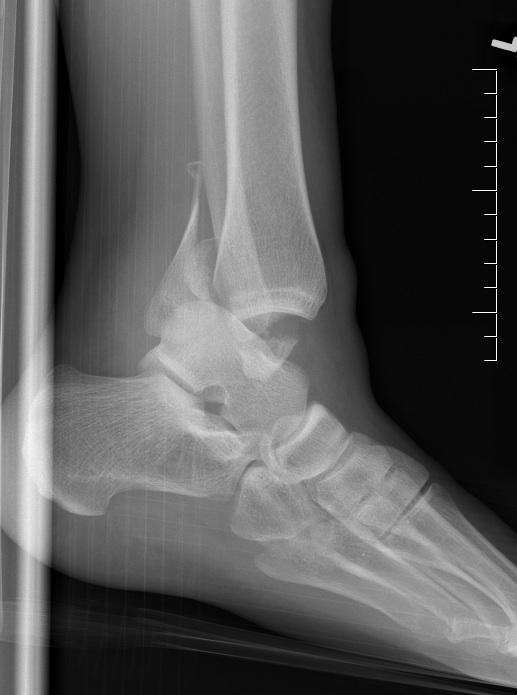

- 90% load through plafond to talus

- 10% load through lateral talofibular articulation

A. Lateral Ligament Complex

ATFL (Anterior Talo-Fibular Ligament)

- tight in plantar flexion